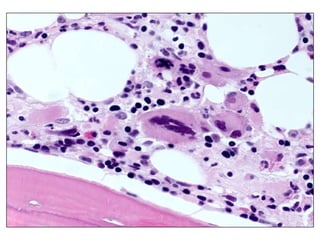

HistologyDensely hypercellular marrow, complete replacement of fat, trilineage hyperplasia. Marked proliferation of immature myeloid cells,  abnormal localization, hypolobularmegakaryocytes, increased reticulin and secondary marrow fibrosis. Immunostains for CD34 shows some positive endothelial cells, few immature hemopoietic cells. The overall proportion of CD34-positive blasts is <5%.

HistologyDensely hypercellular marrow,complete replacement of fat, trilineage hyperplasia. Marked proliferation of immature myeloid cells, abnormal localization, hypolobularmegakaryocytes, increased reticulin and secondary marrow fibrosis. Immunostains for CD34 shows some positive endothelial cells, few immature hemopoietic cells. The overall proportion of CD34-positive blasts is <5%.